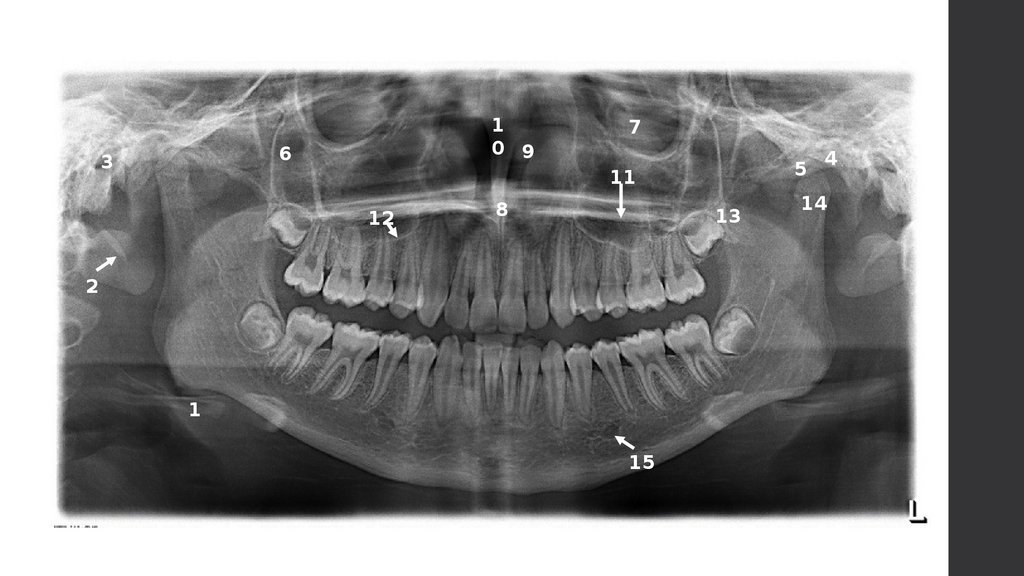

Костные анатомические структуры

на панорамном снимке

1

0 9

6

3

7

5

11

12

8

13

2

15

4

14